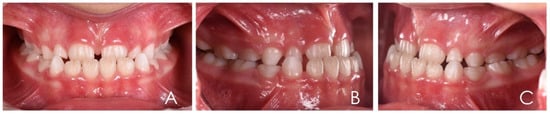

3.1. Clinical Case #1

3.2. Clinical Case #2

3.3. Clinical Case #3

3.4. Clinical Case #4